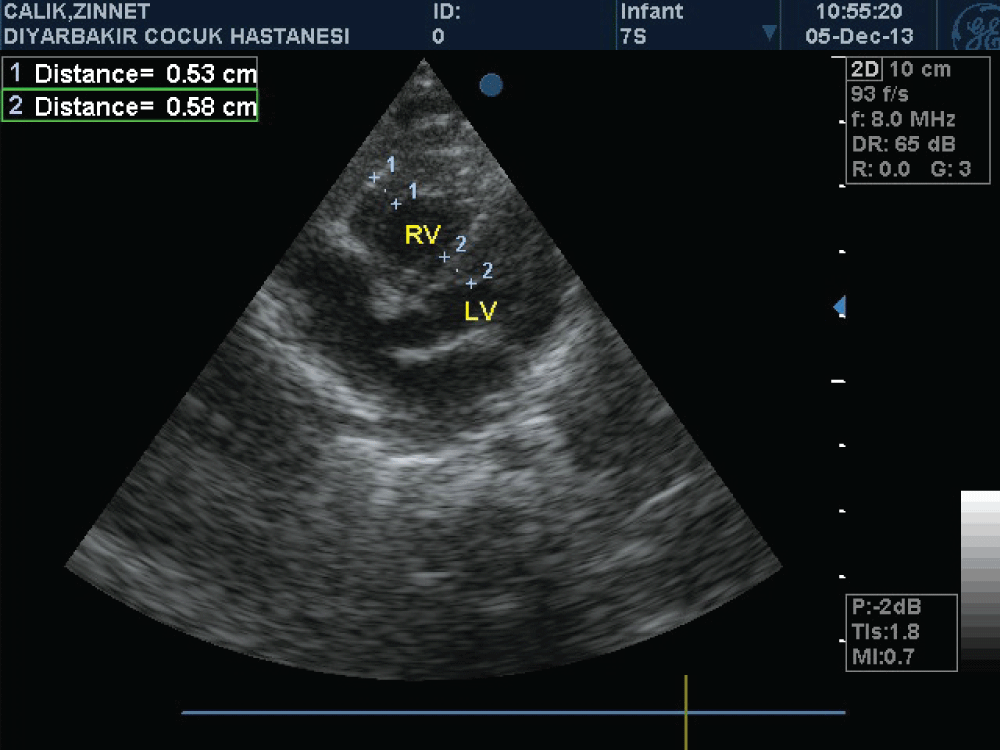

A newborn female patient was admitted to our clinic because of cyanosis. She was born as the first child of non consanguineous healthy parents, via cesarean section due to perinatal stress. Pregnancy was uneventful and family history was unremarkable. There was no history of any medication and gestational diabetes mellitus. Oral glucose tolerance test was normal. Birth weight was 3345 g, and APGAR score at 1 and 5, minute was 6 and 7 respectively. Oxygen saturation on room air was 69%, and was rised to 83% with oxygen supplement. A grade II systolic murmur was present in the tricuspid focus. Transthorasic echocardiographic examination performed at postnatal 6 hour revealed massive hypertrophy in the right ventricle (right ventricular anterior wall thickness was 12 mm, interventricular septum thickness was 12 mm) and grade II tricuspid valve regurgitation (Figure 1). Estimated right ventricular pressure measured through tricuspid regurgitation was 45-50 mmHg. A right to left shunt was observed over a 6 mm diameter secundum type atrial septal defect. The flow in the pulmonary valve was normal and ductus arteriosus was closed. Left ventricular posterior wall thickness was normal (5 mm). There was no coarctation of aorta. Telecardiography was normal. Hemodynamic condition of the patient was thought to be due to the decrease of right ventricular compliance developed secondarily to hypertrophy. To increase right ventricular compliance propranolol was commenced. An oxygen saturation ranged between 83-85% was achieved with the supplementation of 40% oxygen. Saturation values rose up to 90% as of day three and oxygen supplement weaned. The case was discharged oxygen-free and breastfed by the mother on the seventh day. On the day 10 normal saturation values observed and in control echocardiographic examination right ventricular anterior wall thickness measured as 8 mm, while interventricular septum was 6 mm and on the day 40 it was 5.3 and 5.8 mm respectively (Figure 2). Thyroid function tests, Tandem-Mass analysis, and enzyme level for the Pompe's disease were normal.

Figure 1: Massive hypertrophy in the right ventricle (right ventricular anterior wall thickness was 12 mm, interventricular septum thickness was 12 mm)